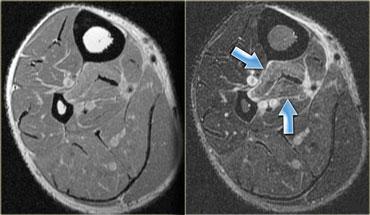

Ở bên trái là hình ảnh của hai bệnh nhân khác nhau với khối máu tụ bán cấp giai đoạn sớm.

Ở ngoài cùng bên trái là hình ảnh T1.

Tín hiệu tăng sáng ở ngoại vi của khối máu tụ là do methemoglobin, xuất hiện sau 2-7 ngày và có thể tồn tại trong nhiều tháng.

Hình ảnh bên phải cho thấy tín hiệu tăng sáng tương tự trên hình ảnh T2.